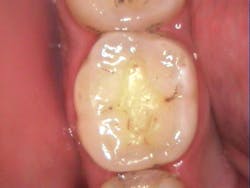

The first case demonstrates a molar with the often-typical A1/B1 shade. It required an occlusal restoration. Following local anesthesia, a DryShield isolation device was placed intraorally. The cavity was accessed and cleaned (figure 1). After rinsing and gentle drying of the dentin, Tokuyama Universal Bond (Tokuyama Dental America), an eighth-generation bonding agent, was applied and dried, without the need for light curing. The Omnichroma composite was built up and cured in 2 mm increments until the tooth was fully restored (figure 2). Note that prior to curing, Omnichroma will appear opaque white. Then, following curing, it immediately blends into the surrounding tooth structure. The occlusion was adjusted, and the composite and surrounding enamel was polished.